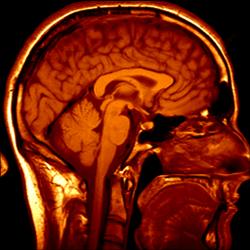

Medical imaging

Image guided surgery

3D imaging

MRI, CT